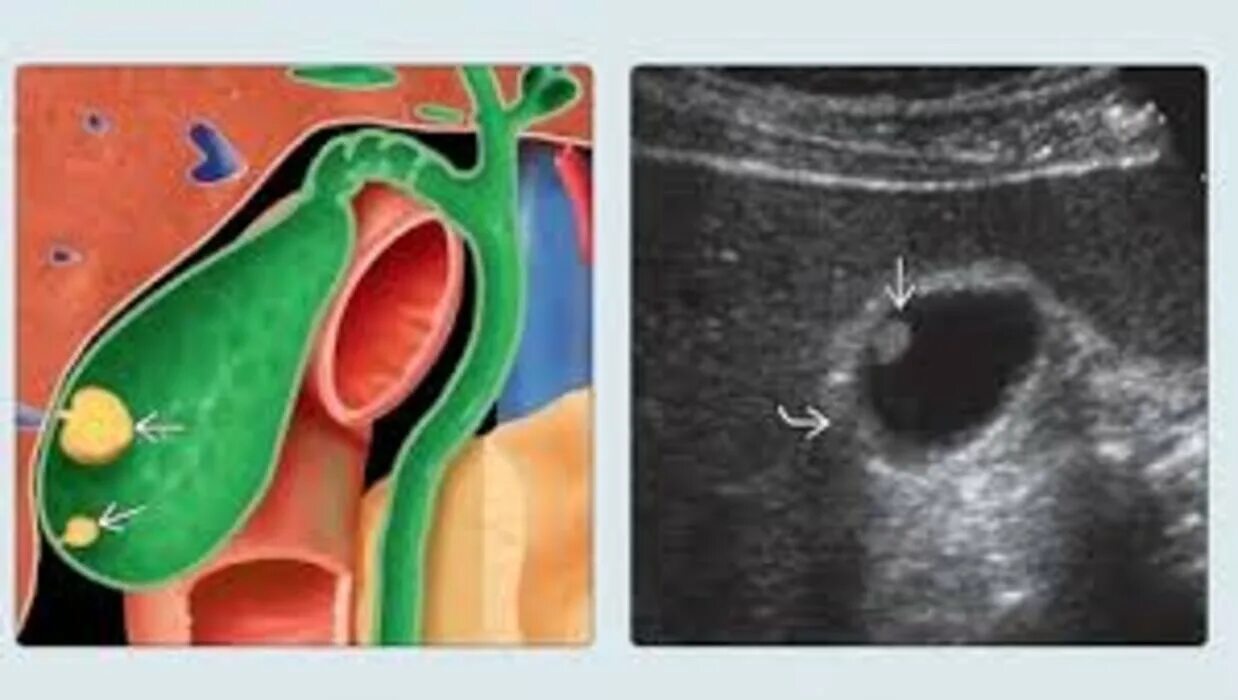

Какие полипы желчного пузыря